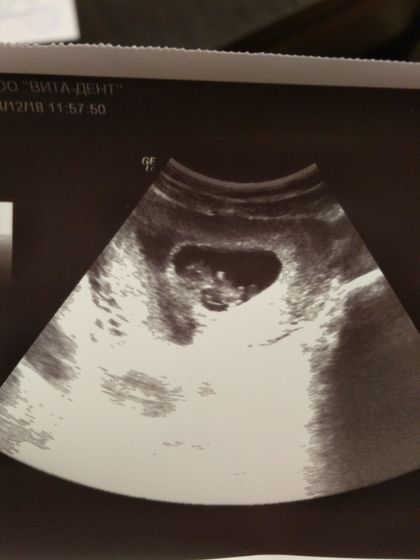

К предыдущему посту ?девочки спасибо, успокоили, к врачу только после 10, она в отпуске, думаю что все Оки будет ❤нет, я уверена ?немного настороженна, но я же мать ?за смотрите какой младенец прекрасный нам машет ❤❤❤

❤Он там как криветка дрыгался ?

По ущи в сантиметрах 2.98 почти 3! боже как быстро время идет, как он вырос